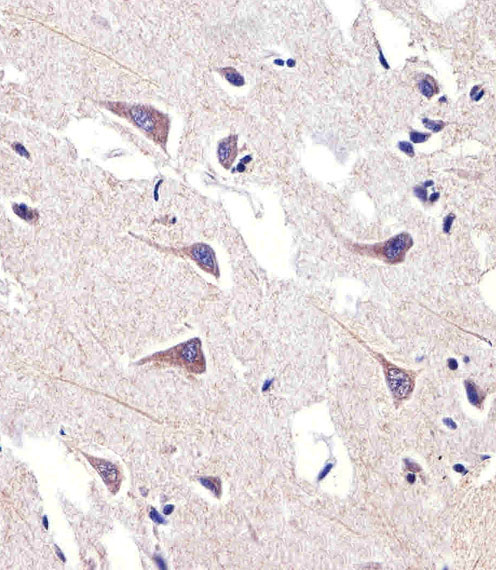

产品名称FADS2 Rabbit Polyclonal Antibody (Center)

推荐应用FCM, WB, IHC-P

稀释度IHC-P 1:100-500, WB 1:1000, FCM 1:10-50